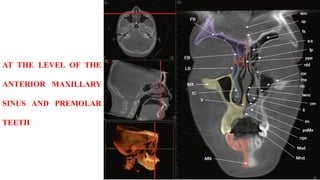

AT THE LEVEL OF THE

NASOLACRIMAL DUCT

MEDIAL WALL OF THE

AT THE LEVELOF THE ANTERIOR MAXILLARY SINUS AND PREMOLAR TEETH